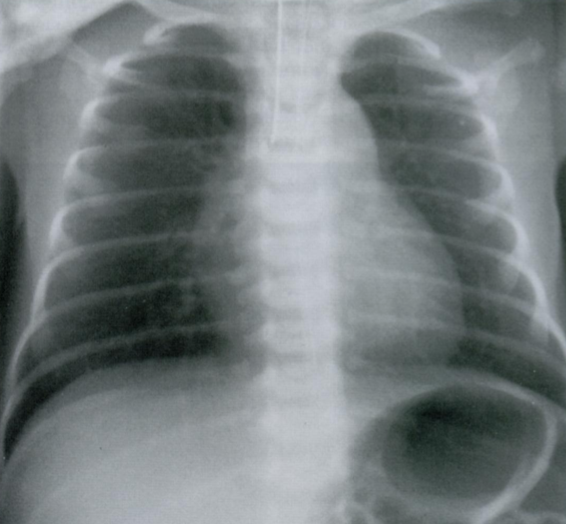

Оцените ассиметричность мягких тканей на снимке.

Обратите внимание на тень молочной железы (стрелочки), оцените симметричность теней слева и справа.

Пациентка после левосторонней мастэктомии с просветлением в нижних отделах с соотвествующей стороны (звездочка) в связи с отсутствием молочной железы (стрелочки).

Если есть сомнения, можно внимательнее рассмотреть подмышечную область на предмет возможного наличия металических клипс после иссечения ЛУ подмышечной впадины (фото ниже).

Ключевой момент - не ошибиться, принимая уменьшение прозрачности с одной стороны за выпот или внутрилегочное образование.